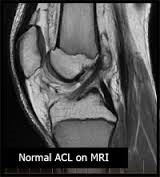

Και με ακέραιους τους δύο χιαστούς